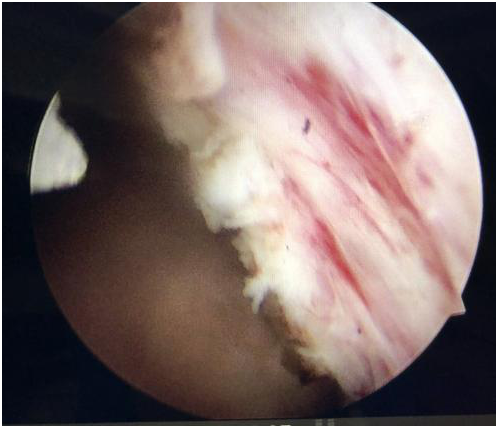

粉碎剜除前列腺組織